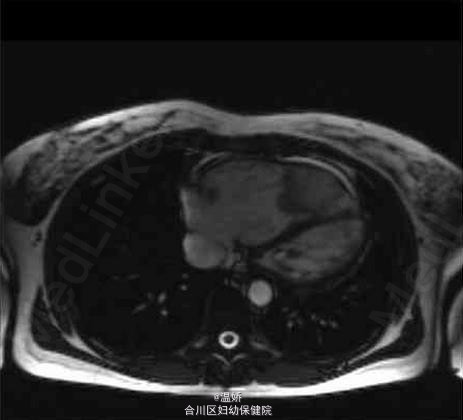

一例罕见的心室粘液瘤

粘液瘤

患者,女,42岁